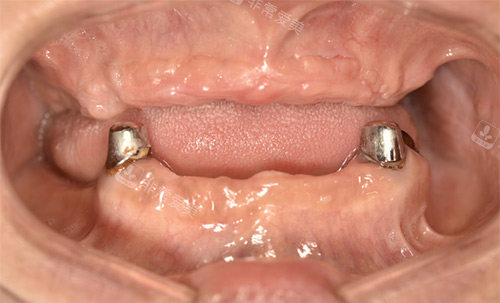

针对骨量不足、牙槽骨萎缩等疑难病例,医院采用国内比较靠前的穿颧穿翼种植技术,实现即刻负重种植,避免传统植骨手术的漫长改善期。

该技术尤其适合半口或全口无牙患者,种植体稳定性强,术后咀嚼功能改善显著。

穿颧穿翼种植全口

多位患者反馈,医院医护团队服务细致,尤其对高难度种植病例的处理结果满意。

例如,一位全口无牙患者通过穿颧种植技术实现当日种牙,术后咀嚼功能显著提升。